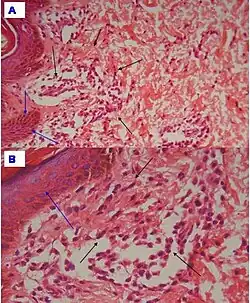

| Urticaria, lymphocyte predominant | Perivascular location. Mast cells are relatively sparse, potentially demonstrated with special stains, preferably tryptase stain. Extravasated erythrocytes are present in about 50% of the cases. No vasculitis.[14] | Dermal edema [solid arrows in (A,B)] and a sparse superficial predominantly perivascular and interstitial infiltrate of lymphocytes and eosinophils without signs of vasculitis (dashed arrow).[15]

| Urticaria, lymphocyte predominant | Perivascular location. Mast cells are relatively sparse, potentially demonstrated with special stains, preferably tryptase stain. Extravasated erythrocytes are present in about 50% of the cases. No vasculitis.[14] | Dermal edema (solid arrows) and a sparse superficial predominantly perivascular and interstitial infiltrate of lymphocytes and eosinophils (dashed arrow)

|